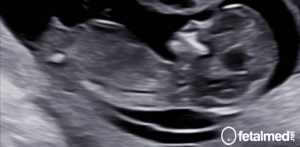

A restrição de crescimento intra-uterino é definida como uma falha do feto em atingir o peso para que foi geneticamente programado. Geralmente ocorre em função de algum fator extrínseco que leva a insuficiência placentária com consequente subnutrição e suboxigenação do feto.

O diagnóstico da restrição de crescimento intra-uterino baseia-se basicamente na estimativa de peso fetal. Para avaliar, use a calculadora de tamanho do bebê por semana. Entretanto é importante observar que uma parcela de fetos podem ser apenas Pequenos para a Idade Gestacional (PIG). O feto pequeno para a idade gestacional possui um baixo peso (abaixo do percentil 10), porém não há um fator limitador externo. O peso fetal é baixo simplesmente pelo fato de que as características genéticas daquele indivíduo o caracterizam desta forma.

Apesar do conceito fisiopatológico da Restrição de Crescimento Intra-Uterino e do Feto Pequeno para a Idade Gestacional serem bastante distintos, a diferenciação entre estas duas situação é extremamente desafiadora na prática diária. Ao ultrassom, o estudo dopplerfluxométrico tem sido utilizado para fazer essa diferenciação uma vez que a insuficiência placentária está associada a alterações de fluxo placentário e fetal.